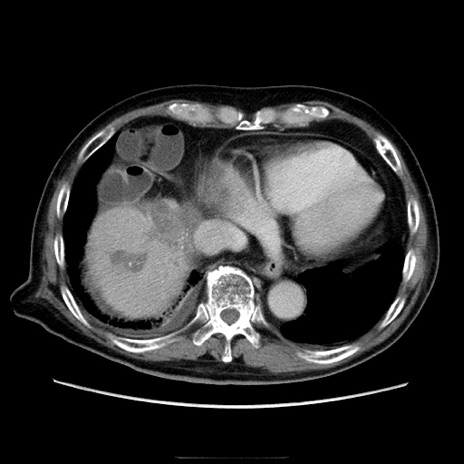

症例21(横断像)

【症例】70歳代男性

【主訴】腹痛

【現病歴】肝硬変・肝細胞癌にてかかりつけの方。約9時間前に食後より腹痛出現。症状が徐々に増悪し、嘔吐出現したため来院。

【既往歴】肝硬変、肝細胞癌(RFA、TACE後)

【身体所見】意識清明、表情苦悶様、BT 36℃、BP 129/78mmHg、P 88bpm、SpO2 97%(RA)、右上腹部から心窩部にかけて圧痛あり、反跳痛なし、筋性防御あり。

【データ】WBC 5800、CRP 0.16